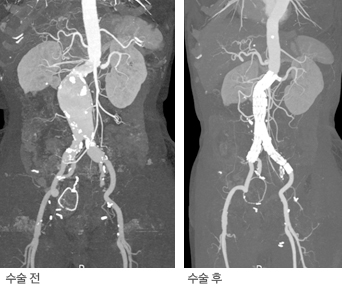

대동맥류 CT 3D 영상

복부대동맥류 수술 전후 CT 3D 영상